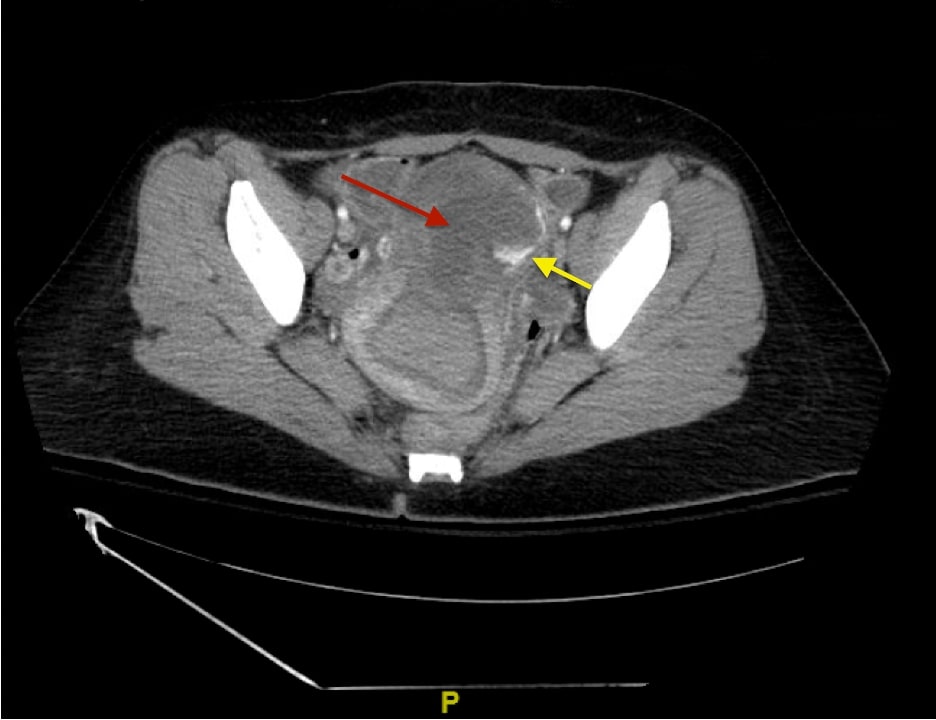

Uterine perforation is a rare but potentially life-threatening complication of gynecologic procedures. Serious complications include hemorrhage, infection, and injury to surrounding organ systems (eg, gastrointestinal, urological, vascular, etc.). Risk factors include advanced maternal age, prior gynecologic surgeries, and other anatomical features that impact the difficulty of accessing the uterine cavity. In this case report, we discuss a patient who presented to the emergency department (ED) with diffuse abdominal pain and vaginal bleeding that occurred after an elective dilation and curettage (D&C) for a termination of pregnancy. The diagnosis was suspected clinically and confirmed by imaging including ultrasound (US) and computed tomography (CT) of the abdomen and pelvis. The patient was managed operatively with a multidisciplinary approach including Gynecology, General Surgery, and Urology. The patient was stabilized and eventually discharged. Uterine perforation should be included in the differential for patients with a history of recent gynecologic instrumentation presenting with abdominal pain and vaginal bleeding. The stabilization of these patients requires aggressive volume resuscitation, controlling the source of bleeding, and emergent surgical consultation.

Topics: Gynecology, vaginal bleeding, ultrasound, computed tomography.